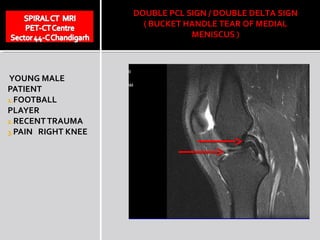

DOUBLE PCL SIGN / DOUBLE DELTA SIGN

( BUCKET HANDLE TEAR OF MEDIAL

MENISCUS )

YOUNG MALE

PATIENT

1.FOOTBALL

PLAYER

2.RECENT TRAUMA

3.PAIN RIGHT KNEE

DOUBLE PCL SIGN

DOUBLE PCL SIGN/ DOUBLE DELTA SIGN ( BUCKET HANDLE TEAR OF MEDIAL MENISCUS ) YOUNG MALE PATIENT 1.FOOTBALL PLAYER 2.RECENT TRAUMA 3.PAIN RIGHT KNEE

DOUBLE PCL SIGN DOUBLE PCL SIGN The detached fragment can place itself in the intercondylar notch ( ventral to PCL ) and this position of the PCL gives double PCL appearance ( DOUBLE PCL SIGN)